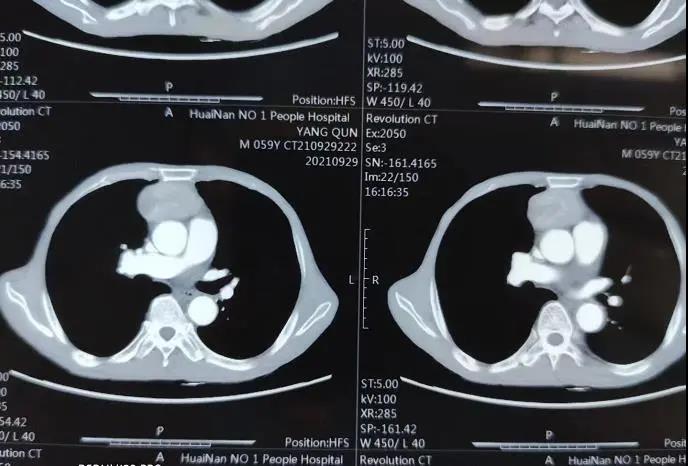

“患者胸腺瘤大约有3CM,入院后完善相关检查,患者没有手术禁忌症,在征得患者及家属意见后,我们手术团队在科室主任、主任医师谢怀顺的指导下,给她做了经剑突下胸腔镜胸腺瘤扩大切除术。”第一附属医院胸外科副主任、副主任医师陶天晓介绍说,整个手术过程完全在胸腔镜下操作完成,手术过程很顺利,完整切除了瘤体和脂肪组织在内的全部胸腺组织,同时保护了双侧膈神经未受损伤,既彻底切除了病变,又达到了微创和美观的效果。